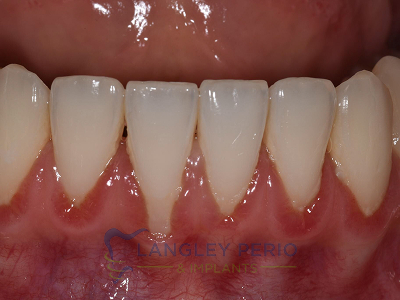

Case 3

Alloderm tissue grafting performed to improve root coverage and esthetics. This technique does not require tissue to be taken from the patient’s palate.